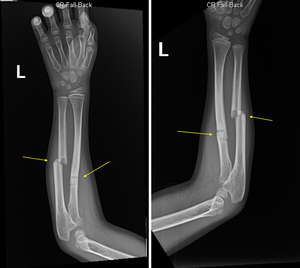

A 7 year old boy presented to the ED following a fall incident on the classroom carpet wherein he landed on his left arm. He arrived with a chief complaint of pain throughout his left arm. A physical exam revealed tenderness to palpation mid shaft and neurovasculature remained intact. Bone density was within normal limits, and the patient denied any fevers, chills, chest pain, shortness of breath, nausea, vomiting, diarrhea, abdominal pain, headache, or urinary symptoms. The patient had decreased conspicuity of the ulna and had a partial fracture of the mid radial diaphysis with 20-30% overriding of the fracture fragments. There was a mildly angulated fracture of the radius in the proximal/mid region. Two views of the fracture were obtained (figure 1).

Three months earlier, the patient experienced an accident leading to greenstick fractures of the mid radial and ulnar diaphyses with volar angulation in his left arm. One month prior, the patient had come out of casting, wore a splint for approximately a week, and then allowed the arm to heal without any assistive devices. During the current visit, the patient was provided a full splint and prescribed 200 mg of ibuprofen.